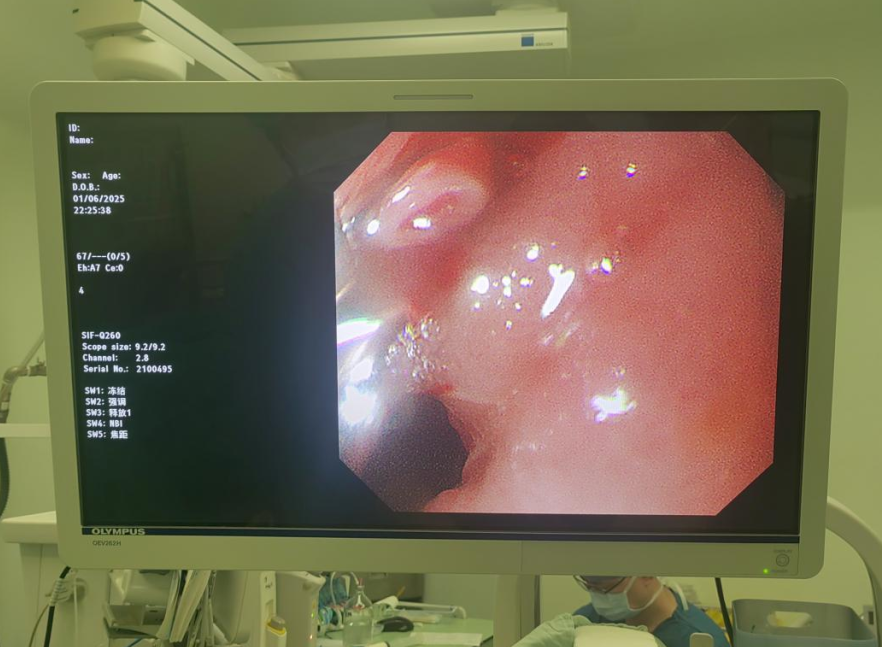

在各方全力支撑下,内镜中心何金贵医师团队凭借精湛技术,克服重重困难,经口深入小肠细致探查。最终在小肠空肠段发现多发憩室,并精准定位到一处憩室口破裂的动脉血管(直径约0.5cm)。

何医师迅速使用止血夹成功封闭血管,出血即刻停止。术后患者转危为安。